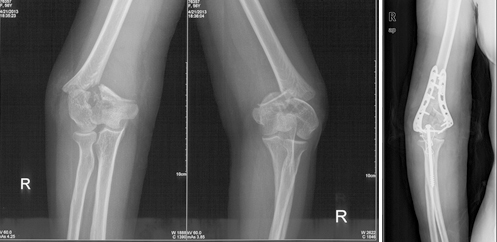

2、老年骨质疏松骨折的治疗:

随着我国人口老龄化,骨质疏松骨折发病率连年上升,髋部骨折、脊柱压缩骨折、桡骨远端骨折、肱骨近端骨折四大骨质疏松骨折成了困扰老年人的常见病和多发病。一旦发生骨质疏松骨折,轻则致残,重则由于卧床并发症造成死亡,对于家庭和社会造成沉重负担。北京清华长庚医院创伤骨科中心应用髓内钉、椎体成形等微创技术,结合传统的钢板螺钉固定、关节置换等手术方案,为多名90岁以上超高龄老人进行了手术,获得术后第1天即可下地行走的良好效果,让更多骨折后的老人重返社会。

高龄老人髋部骨折髓内钉微创治疗,术后即可下地恢复活动。